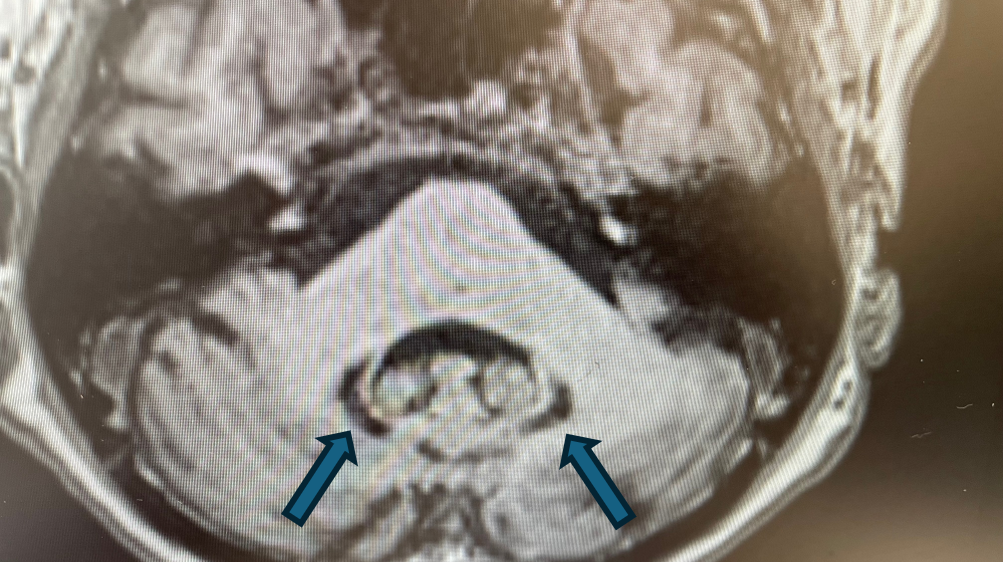

Rycina 4. Cechy akumulacji jonów żelaza w obrębie jąder zębatych móżdżku (T1).

rycinka